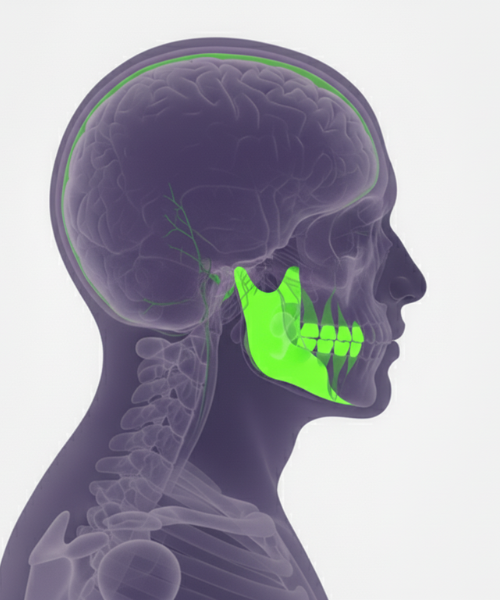

Comprehensive MRI examination of the temporomandibular joint to diagnose jaw pain, clicking, and movement disorders with precision.